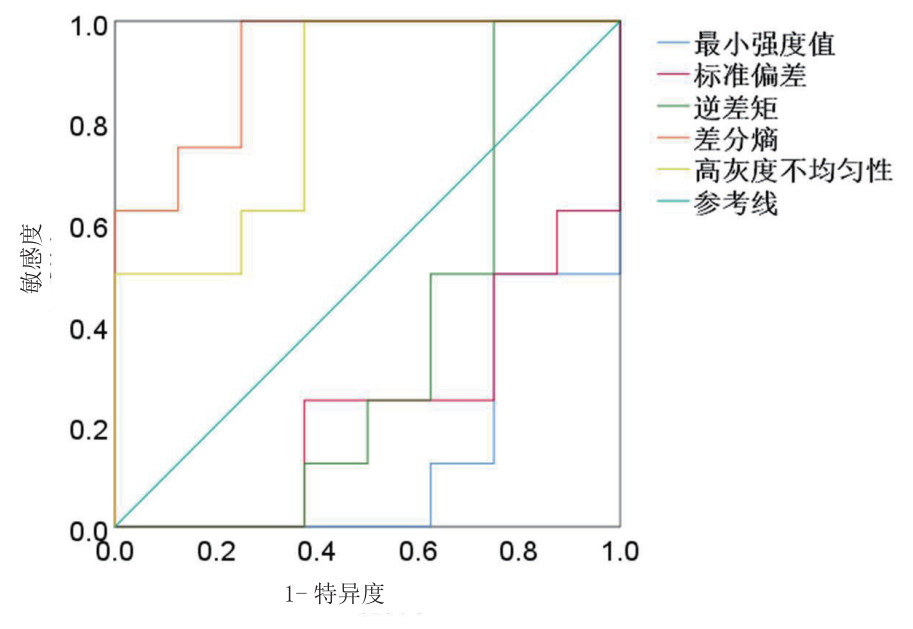

两组大鼠全脑T2WI图像均未见异常信号(图 1)。提取基于T2WI图像的纹理特征共68个,包括27个直方图特征,9个形态学度量特征,22个灰度共生矩阵特征和10个游程长矩阵特征;其中35个(35/68,51.5%)纹理特征ICC>0.8。在35个ICC>0.8的特征中,两组间直方图特征(最小强度值、标准偏差)、灰度共生矩阵特征(差分熵、逆差矩)及游程长矩阵特征(高灰度不均匀性)的差异均具有统计学意义(均P < 0.05,表 2)。运用ROC曲线评价上述纹理特征中CA/CPR后脑损伤的诊断效能(图 2),其中差分熵诊断效能最优(AUC=0.922),取阈值为0.512时,其评价CA/CPR后脑损伤的敏感度为100%,特异度为75%,其余参数诊断效能见表 3。

| 差分熵诊断效能最优,敏感度为100%,特异度为75% 图 2 大鼠全脑T2WI纹理特征ROC曲线分析 Fig 2 ROC curve analysis of whole brain T2WI texture characteristics in rats |